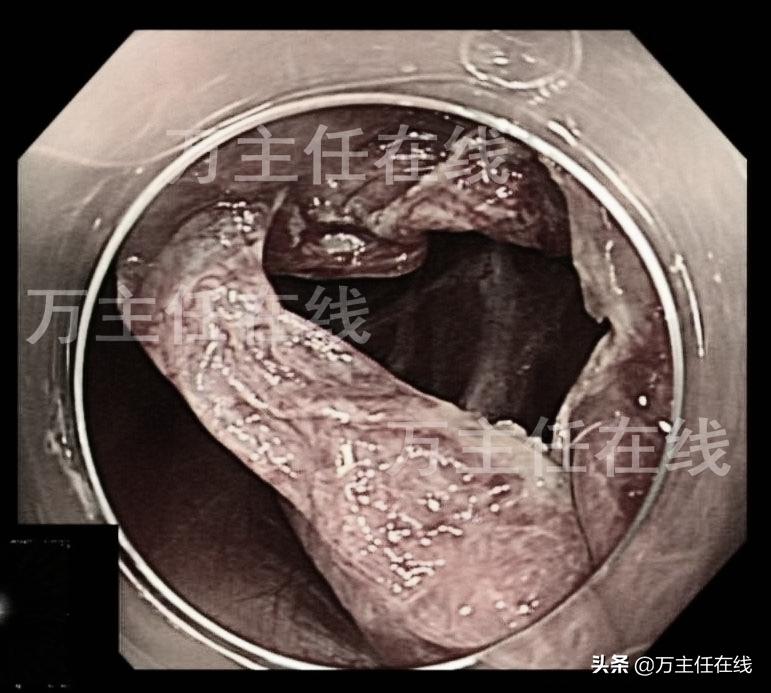

肝囊肿内镜下表现

内镜直视下穿刺引流囊液

内镜直视下打开囊壁(注:原图片可能引起不适已调整)

囊腔内的表现

以圈套器依次切除囊壁(注:原图片可能引起不适已调整)

已切除囊壁后的肝囊肿(注:原图片可能引起不是已调整)